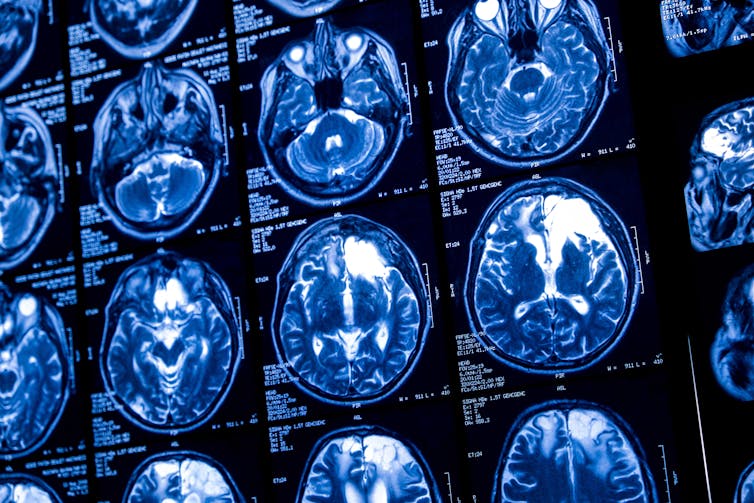

There are many correlations between our brain states and our thoughts. Certain parts of the brain predictably “light up” when someone is in pain, or if they think about the past or future.

The hippocampus, located near the brain stem, appears to be linked to imaginative and creative thought, while the Broca’s area in the left hemisphere appears to be linked to speech and language.